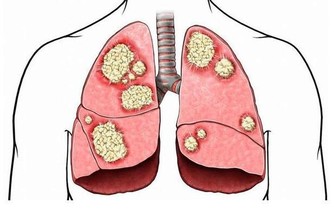

大腸癌是與飲食習慣密切相關的疾病,隨著經濟水平提高,生活富裕,食物越多,吃得越好,大腸癌也變得越“活躍”。在我國,每年有14萬人被確診患大腸癌,而且發病率每年遞增2.5%~5.0%,遠遠高於全球平均水平的2%。

及時發現和治療,90%的大腸癌患者可以得救。所以,定期體檢很重要!

建議:一般人群50歲開始接受大腸癌的篩查,每5~10年進行一次檢查,檢查主要包括大便隱血和腸鏡。高危人群可提前到40~45歲左右,平均每3~5年接受一次檢查。